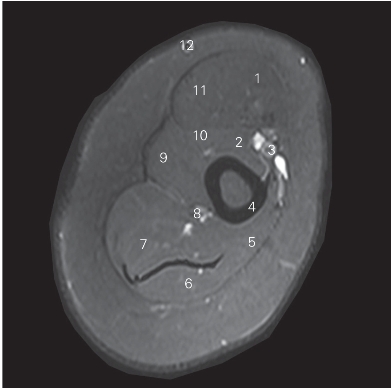

图4-27 经臂中份的横断层MR T2WI FS

1 肱二头肌短头 short head of biceps brachii

2 喙肱肌 coracobrachialis

3 肱动脉 brachial artery

4 肱骨 humerus

5 肱三头肌内侧头 medial head of triceps brachii

6 肱三头肌长头 long head of triceps brachii

7 肱三头肌外侧头 lateral head of triceps brachii

8 桡侧副动脉 arteriae collateralis radialis

9 三角肌 deltoid

10 肱肌 brachialis

11 肱二头肌长头 long head of biceps brachii muscle

12 头静脉 cephalic vein